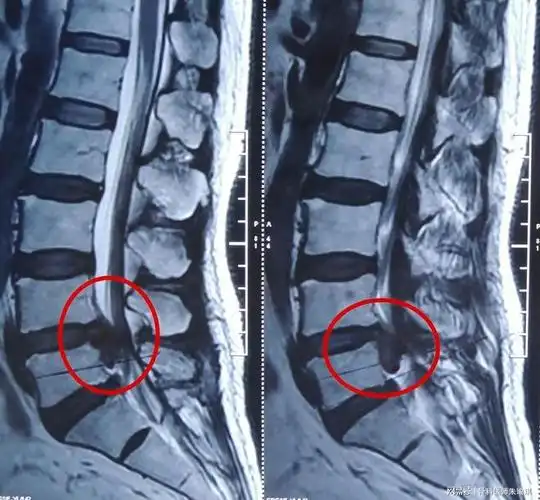

腰椎间盘突出症